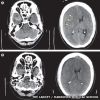

L'heavy metal può davvero darvi alla testa. O almeno questo è quel che è successo ad un fan cinquantenne dei Motorhead alcuni mesi fa, mentre si esibiva in un headbanging esagerato che gli ha provocato un coagulo di sangue al cervello.

Dopo anni di headbanging, l'uomo aveva iniziato a percepire i sintomi di un'emicrania fortissima che non accennava a smettere o a diminuire; i medici hanno collegato il disturbo alla costante attività metallara dell'uomo, che era solito andare ai concerti con suo figlio.

Questo è il quarto caso di ematoma cerebrale collegato all'headbanging (di cui uno ha portato alla morte del paziente), che può provocare seri danni al cervello facendolo "rimbalzare" contro il cranio.